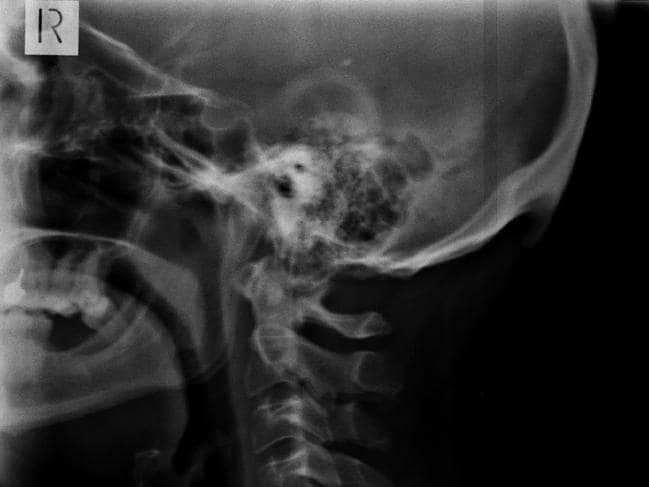

Dos investigadores australianos hicieron el extraño descubrimiento mientras examinaban cientos de radiografías de personas entre 18 y 30 años, observando que casi la mitad había desarrollado crecimientos óseos que normalmente se pueden ver en personas ancianas que han mantenido una mala postura a lo largo del tiempo, generalmente encorvada.

Lee también: Delgado oso polar caminó más de 1.500 kilómetros buscando comida y llegó a la ciudadEncontrar este crecimiento craneal con forma de "cuernos" preocupó a los australianos, quienes atribuyeron la formación a las tecnologías modernas. Los hallazgos del Dr. David Shahar y el Profesor Asociado Mark Sayers de la University of the Sunshine Coast, dejaron ver los resultados de su investigación a fines del año pasado.

El estudio sostiene que se están formando estos cuernos en base al análisis que de 218 radiografías de personas de 18 a 30 años de edad. Determinaron que de ellas el 41% había desarrollado un bulto óseo de 10 a 30 milímetros en la parte posterior de su cráneo.